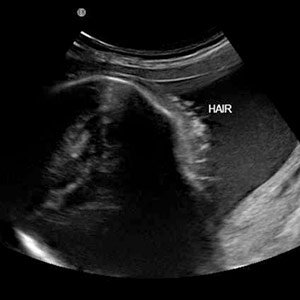

А и още. Когато коментирахте дали може да се види косата на бебето на преглед с ехограф- може, но по-добре се вижда на 2Д, а не на 3Д/4Д.

Ето снимка от нета: